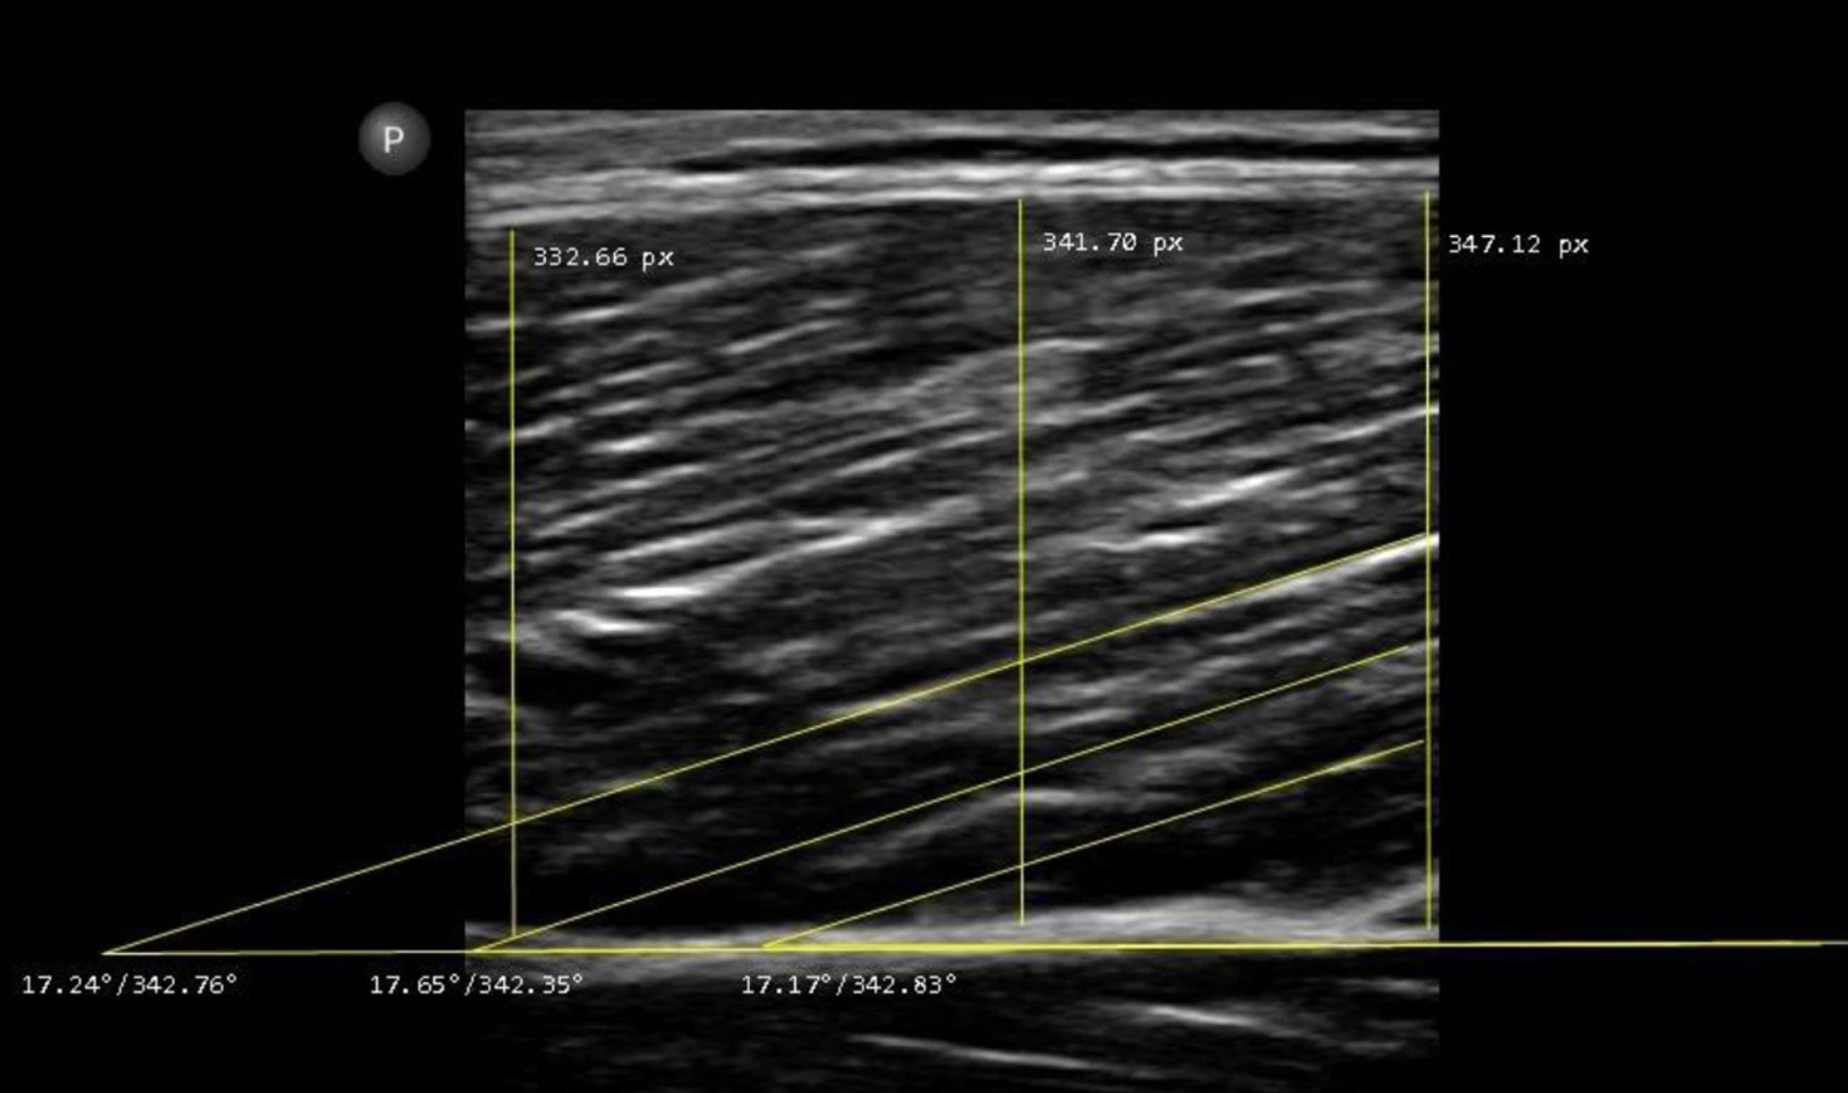

The precision error for BMD measured via dual-energy X-ray absorptiometry (DEXA) can be close to the rate of increase or decline that one might see from annual aging or from the interventions listed above [8, 9]. Therefore, one would likely want to see an improvement beyond 1-2% to know that they overwhelmed the technical error of the device and operator. This metric could be tracked annually or every other year ideally utilizing the same positioning and scanning facility.